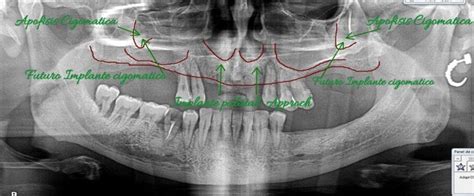

- Implantes cigomáticos: Son una alternativa ideal cuando no es posible realizar un injerto óseo en el maxilar superior.

Implantes de Carga Inmediata: Un Protocolo Simplificado

El objetivo de este artículo es presentar, mediante un reporte de caso, un protocolo simplificado para la instalación inmediata de una prótesis definitiva sobre 4 implantes posicionados en la zona anterior de la mandíbula. Mediante este protocolo el paciente con imposibilidad de utilizar una prótesis convencional podrá recuperar su función masticatoria de manera rápida, fácil de llevar a cabo tanto para el clínico como para el laboratorio y con bajos costos.

La planificación se realizó por medio de una ortopantomografía, evitando la utilización de cone-beam, siguiendo nuestro objetivo de realizar un tratamiento con un bajo costo. Al momento de la cirugía la paciente se encontraba premedicada con amoxicilina de 500mg cada 8h desde el día anterior, ibuprofeno 400mg cada 8h, comenzando 1h antes de la cirugía y colutorios de clorhexidina al 0,12%, habiendo iniciado el tratamiento 48h antes del procedimiento quirúrgico.

En el pabellón se probó nuevamente la guía multifuncional en boca, se anestesió a la paciente para luego realizar una incisión crestal desde la zona del primer molar derecho a la zona del primer molar izquierdo, con incisiones liberadoras bilaterales, para luego realizar la disección subperióstica lingual y vestibular. Con la plantilla radiográfica proporcionada por el fabricante se seleccionó sobre la radiografía panorámica el largo de los implantes a colocar.

La cantidad de tejido óseo en sentido vestíbulo-lingual observada durante la cirugía fue de 5-6mm, por lo que los implantes utilizados fueron implantes cónicos Strong SW de hexágono interno (SIN®, Sao Paulo, Brasil) de 3,8mm de diámetro. Con la ayuda de la guía como referencia, se colocó 2 implantes distales, uno en cada lado, en la zona de los primeros premolares, inclinados a distal, teniendo una longitud de 13mm. Otros 2 implantes se colocaron a cada lado de la línea media mandibular, con una longitud de 15mm. Se comprobó que los 4 implantes tuviesen una estabilidad primaria superior a los 30N/cm. Se instalaron pilares Mini-Abutment y cilindros de protección de pilar, también teniendo como referencia la guía multifuncional. Se eligió suturar los tejidos con sutura no reabsorbible 4-0 (Seda, Ethicon, Johnson & Johnson, Brasil), siguiendo nuestro objetivo de disminuir los costos del procedimiento, y se envió a la paciente a la sala de recuperación.